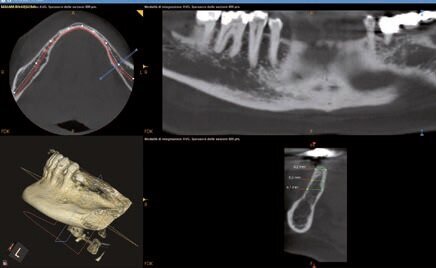

Questo consentirà di sfruttare al meglio la disponibilità ossea in relazione alle necessità protesiche. Per realizzare il sito implantare è stata messa a punto una speciale guida chirurgica, di sezione rettangolare e adeguata alla forma degli specifici inserti piezochirurgici per la preparazione del sito. Si presenta all’osservazione una paziente di 53 anni che presenta mobilità di grado 2 a carico del manufatto protesico 35-x-x-38. Radiograficamente si riscontra un riassorbimento radicolare dell’elemento 35. Si procede ad effettuare una cone beam per l’eventuale sostituzione implanto- protesica degli elementi 35-36-37.

Dalla cbct si evince che la cresta ossea è anatomicamente sfavorevole. Un’ipotesi di piano di trattamento era:

Fig. 2 - Misurazioni in sede 35.

Fig. 3 - Misurazioni in sede 37.

Fig. 4 - Progettazione impianto 35.

Fig. 5 - Progettazione impianto 37.

Fig. 6 - Progettazione dima chirurgica.